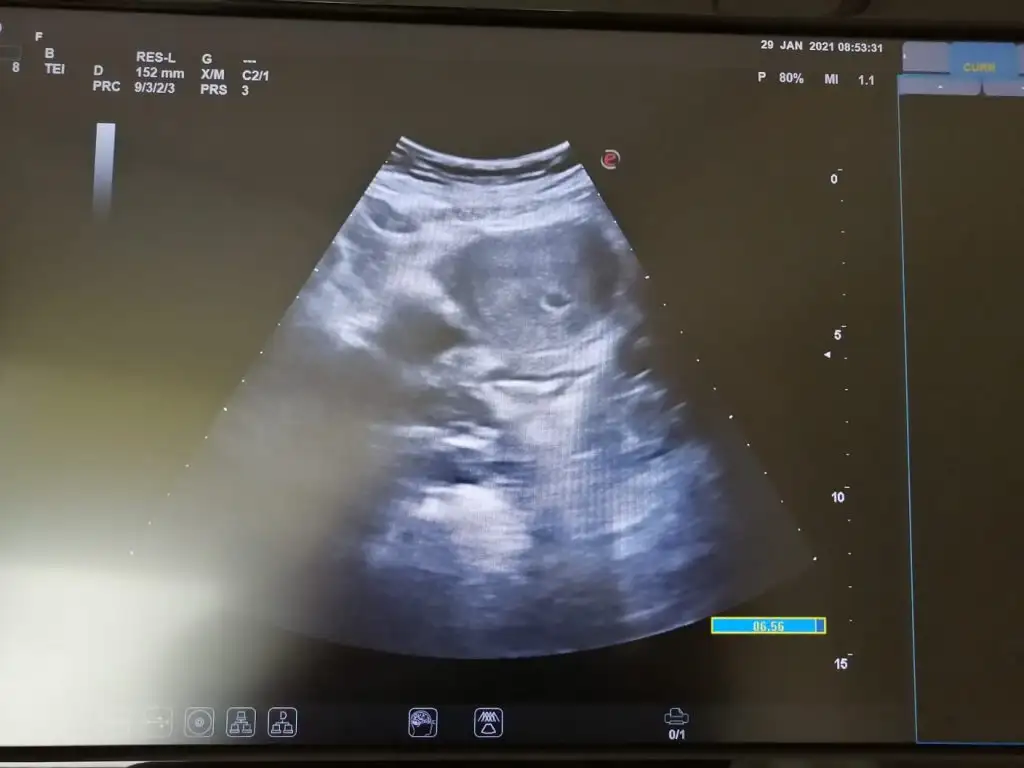

Sizinle paylaşmak istedim. Ultrason fotosundan anlayan var mi? nor